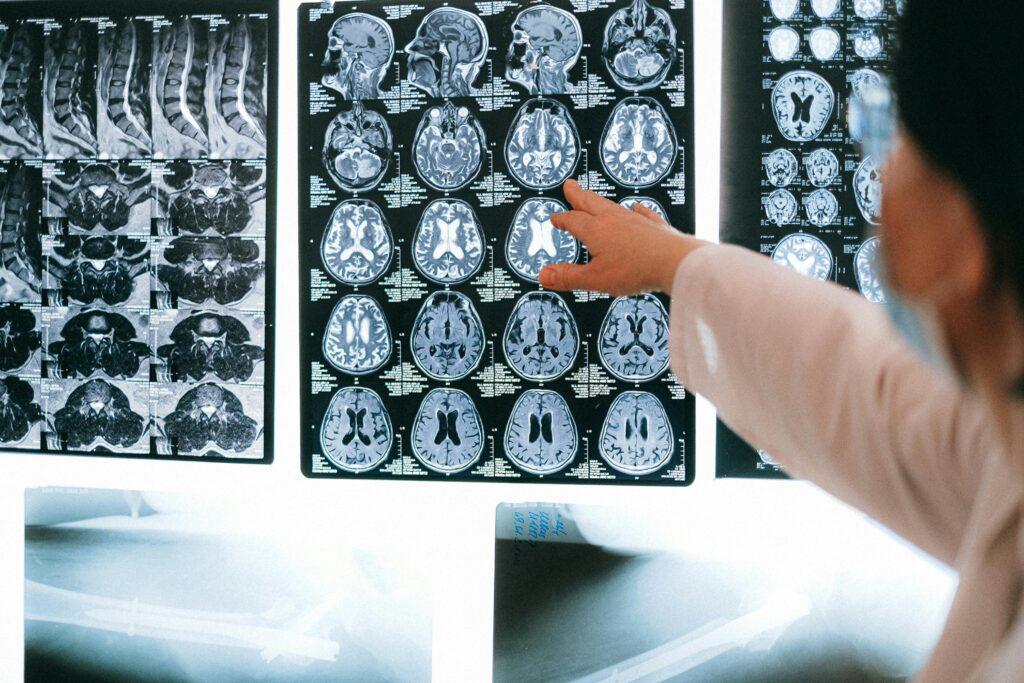

How to Help a Family Member Who Suffered a Traumatic Brain Injury in NYC